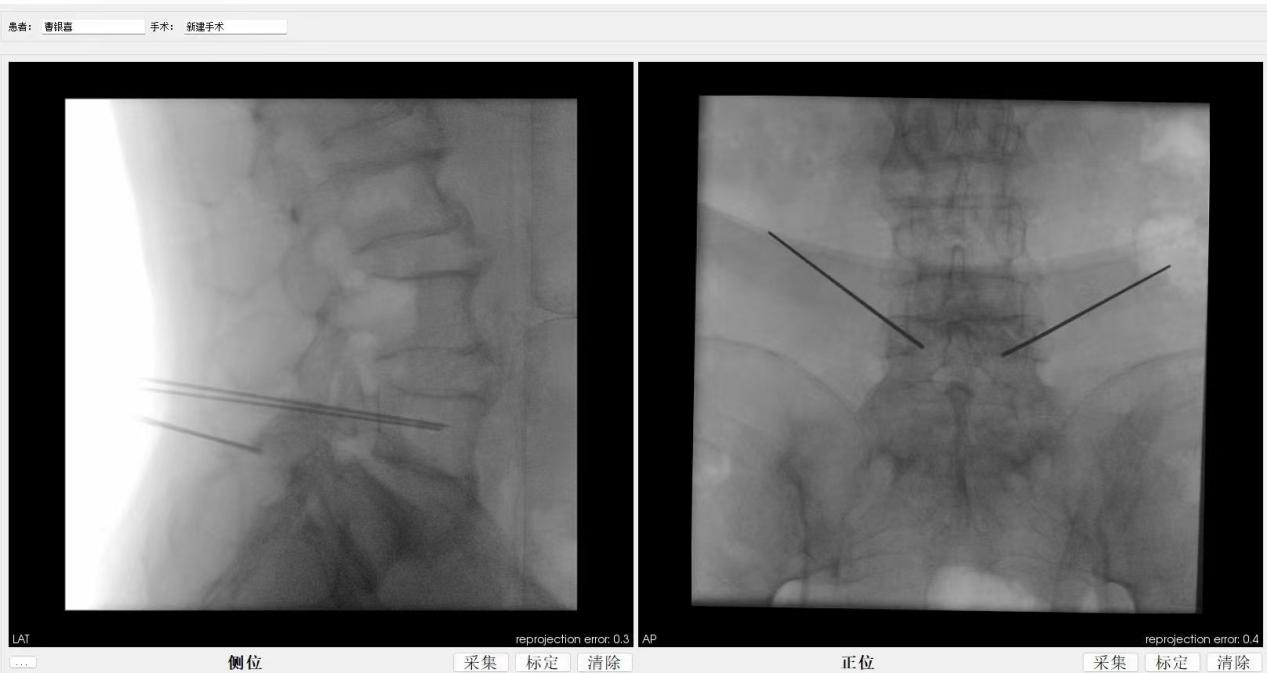

ORTHBOT脊柱机器人术前设计及术中穿刺

患者64岁,因间断性腰痛30年,加重伴间隙性跛行2年,辗转北京及西安多所医院,均建议采取传统外科开放手术治疗,患者因担心手术风险,迟迟不愿手术。经多方打听,患者慕名找到李全义主任医师。入院后李全义主任医师仔细研究患者的疾病特点,经过充分的沟通,决定采用目前骨科先进的微创、精准技术—机器人辅助微创手术。李全义主任医师团队顺利为患者实施ORTHBOT脊柱机器人辅助镜下腰5椎体滑脱复位椎管减压椎间融合内固定术,以机器人辅助微创手术解决了患者的痛苦,减少手术创伤及并发症,缩短手术时间。手术利用术前患者的影像学资料,模拟建立穿刺路径及各项参数,极大地优化手术方案使其更加精准、安全、有效,显著降低了制钉过程中神经根损伤的风险。